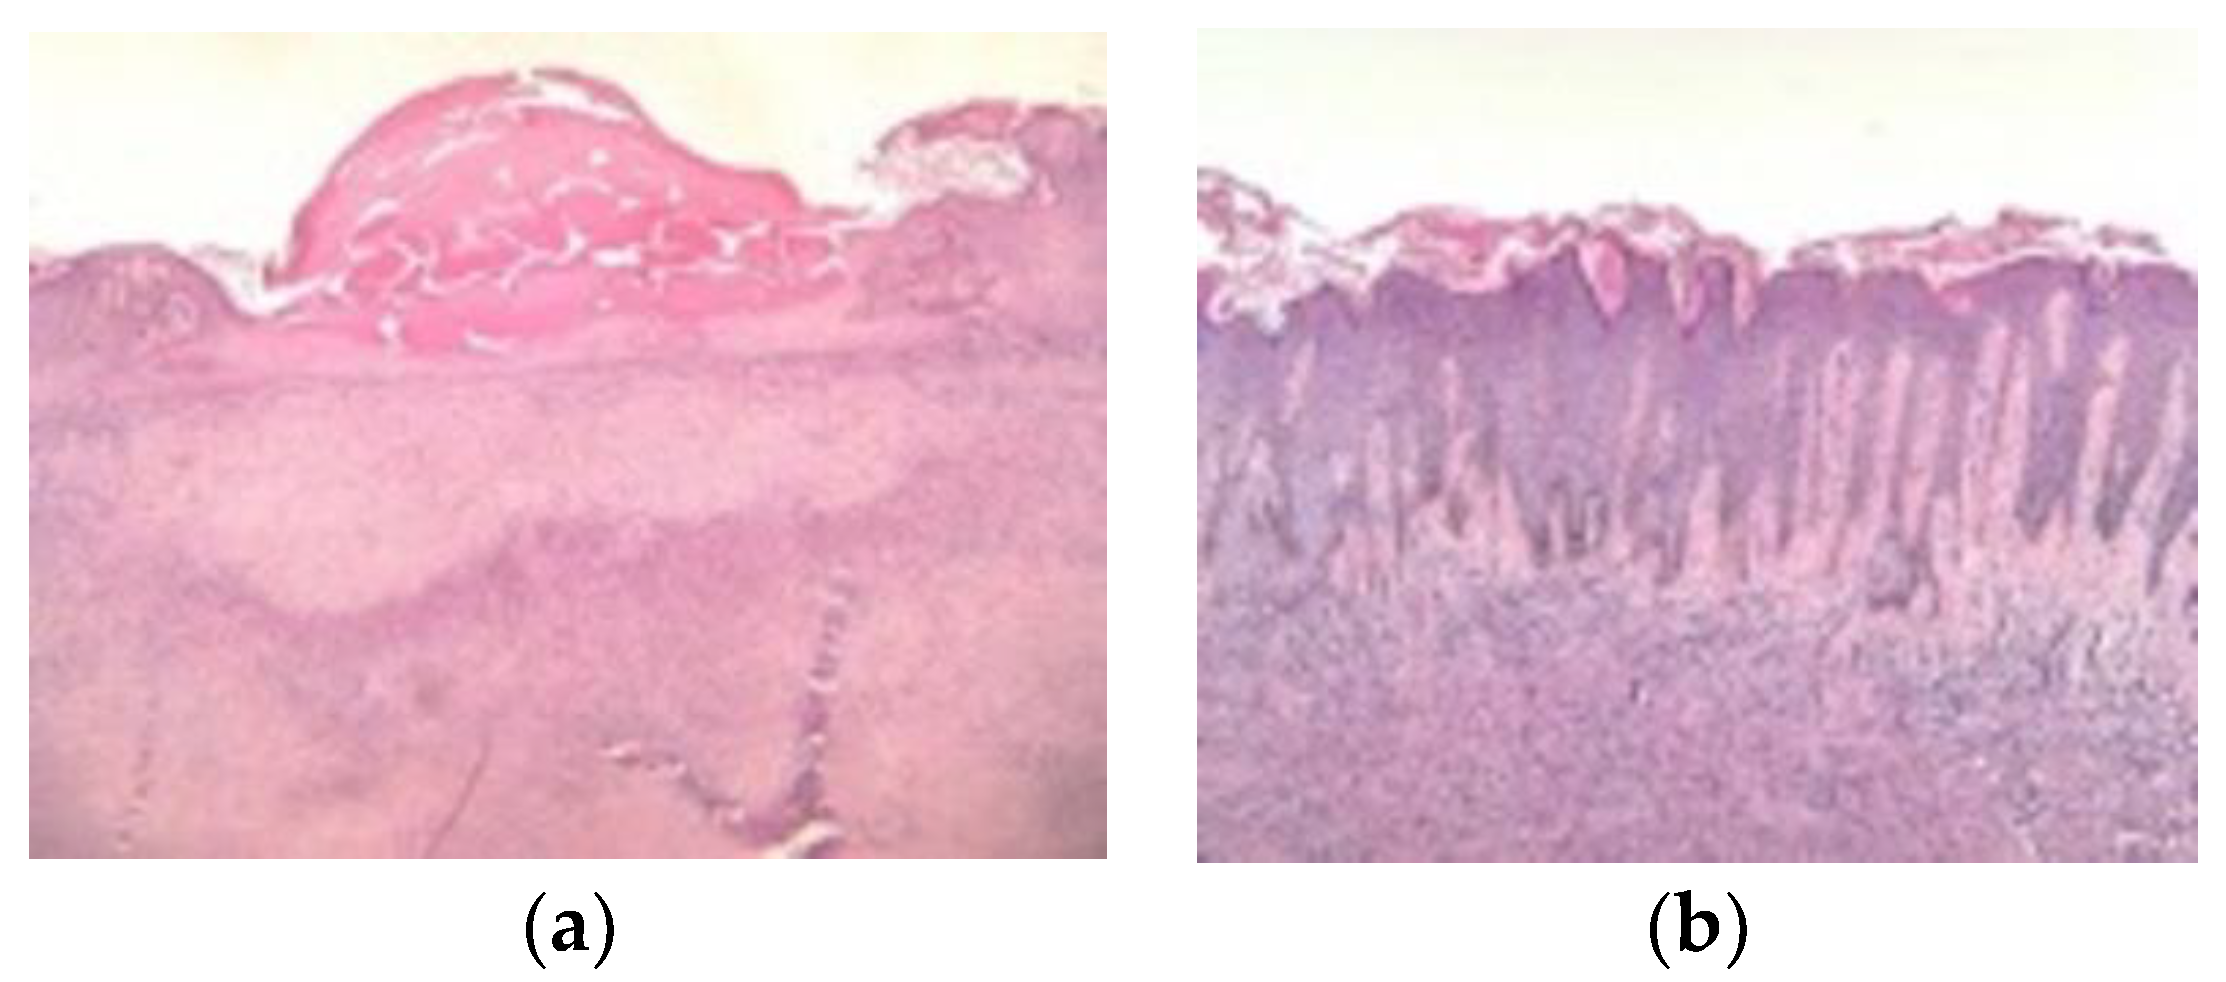

3.3. Histologic Variants